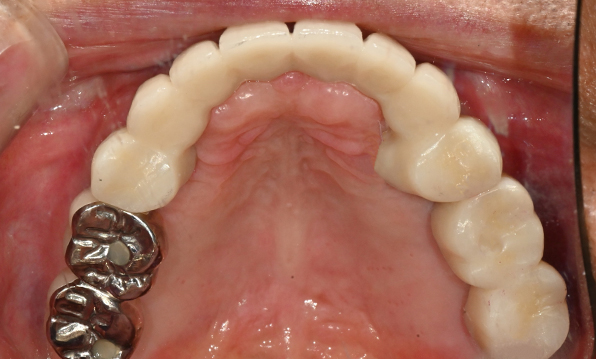

전체 임플란트

위 아래 치아가 정확하게 맞아야하는 고난이도 임플란트

임상 경험이 많은 숙련된 전문의의 섬세한 기술력이 중요합니다.

정확성 높은 식립의 노하우

3D 디지털 진단을 통한 체계적인 계획

전체 임플란트는 위턱과 아래턱의 교합, 잇몸뼈의 상태 및

얼굴 변화 등 모든 것을 고려해 식립해야 합니다.

서울더자연치과는 3D 디지털 기술의 정밀 진단을 바탕으로

수술 계획을 세워 수술을 집도합니다.

치료기간 : 2021.04.12~2021.09.15